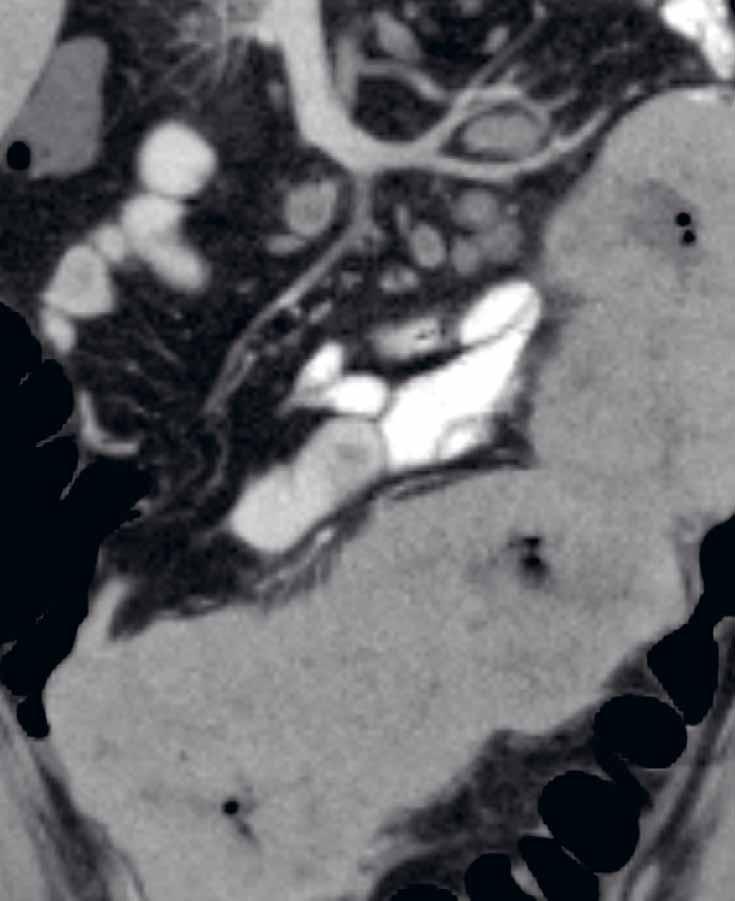

2.3.1 CT enterografie (enteroklýza)

CT enterografie a enteroklýza jsou metody k cílenému posouzení tenkého střeva. Využití mají zejména u pacientů s IBD v akutních i chronických stavech. K dostatečnému posouzení tenkého střeva a jeho případných patologií je u obou metod nutná dostatečná distenze tenkého střeva, kterou docílíme aplikací luminálních kontrastních látek.

U CT enterografie je kontrastní látka podávána orálně, frakcionovaně. Při klasické

CT enterografii volíme pro detailnější hodnocení střevní stěny perorální aplikaci neutrální kontrastní látky (například manitolu). V průběhu 50 minut aplikujeme 1,5–2 litry roztoku kontrastní látky per os. Při cíleném podezření na píštěle, kolekce či dehiscence anastomóz využíváme pozitivní kontrastní látky, například baryovou suspenzi či jodový roztok. Nežádoucí spazmy tenkých kliček eliminujeme intravenózním podáním spazmolytika těsně před vyšetřením.

U CT enteroklýzy je kontrastní látka aplikována nazojejunální sondou a je zde udávána o něco větší senzitivita i specificita v detekci a hodnocení postižených segmentů. Při CT enteroklýze se nejdříve zavede nazojejunální sonda a následně jsou pumpou aplikovány asi 2 litry manitolu.

Rozsah vyšetření u obou metod zahrnuje oblast břicha a malé pánve a provádí se nativně a dále po aplikaci jodové kontrastní látky intravenózně (i.v.). Většinou se zhotovuje jedna postkontrastní fáze, tzv. fáze enterální. Při dalším požadavku, například na zmapování arteriálního řečiště před rozsáhlejšími resekcemi, je nutné provedení i arteriální fáze. Možností multiplanárních rekonstrukcí (MPR) se výrazně zlepšuje hodnocení anatomických vztahů a vztah patologie k okolním strukturám (zobrazení v koronální i sagitální rovině). Další softwarová vybavení umožňují podrobnější postprocesingové zpracování (například „curved MPR“, kterou lze využít ke stanovení délky postižených úseků či délky reziduálního střeva při syndromu krátkého střeva).